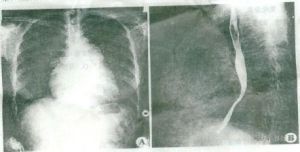

X線檢查肺透明度增加。但在早期這一X線徵象不夠敏感。重度肺氣腫時胸廓飽滿,肋骨走行變平,肋間隙增寬。側位片胸廓前後徑增大,胸骨後間隙過寬。膈肌位置下移,膈穹窿變為扁平。兩肺透明度增高,肺野外帶血管紋理纖細、稀疏。心影呈垂直狹長。透視下可見胸廓和膈肌活動度減弱。也有表現為肺紋理增多的,肺透明度增高不明顯,肺門部肺動脈增寬,心臟常擴大。